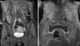

Thrombosis of pelvic veins

Pelvic congestion syndrome, also known as pelvic vein incompetence, is a long term condition in women believed to be due to enlarged veins in the lower abdomen. The condition may cause chronic pain, such as a constant dull ache, which can be worsened by standing or sex. [Source: Wikipedia ]